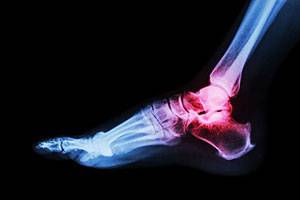

Расширенное рентгенологическое исследование при повреждениях голеностопного сустава и стопы

Переломы костей стопы и голеностопного сустава являются самыми частыми повреждениями скелета. Их доля, по свидетельству разных авторов, составляет не менее 10–15%.

Переломы костей стопы и голеностопного сустава являются самыми частыми повреждениями скелета. Их доля, по свидетельству разных авторов, составляет не менее 10–15%.Особенностью этих переломов является высокая частота внутрисуставных повреждений, при лечении которых неудовлетворительные результаты достигают 28%. Аналогичная тенденция прослеживается при переломах костей стопы.

Наибольшее клиническое значение имеют повреждения пяточной и таранной костей. Так,переломы пяточной кости составляют около 60% от переломов костей предплюсны и 2% от всех переломов. Результаты консервативного лечения чаще неудовле-творительные. Переломы пяточной кости в 75% случаев вовлекают подтаранный сустав; при этом 80% из них сопровождаются смещением отломков.

Отсюда несоответствие и нарушение конгруэнтности суставных поверхностей,ранние дистрофические изменения, поздние болевые атаки и инвалидизация. Учитывая,что большая часть больных с переломами костей стопы и голеностопного сустава – трудоспособные люди, становится ясной необходимость их детального лучевого обследования.